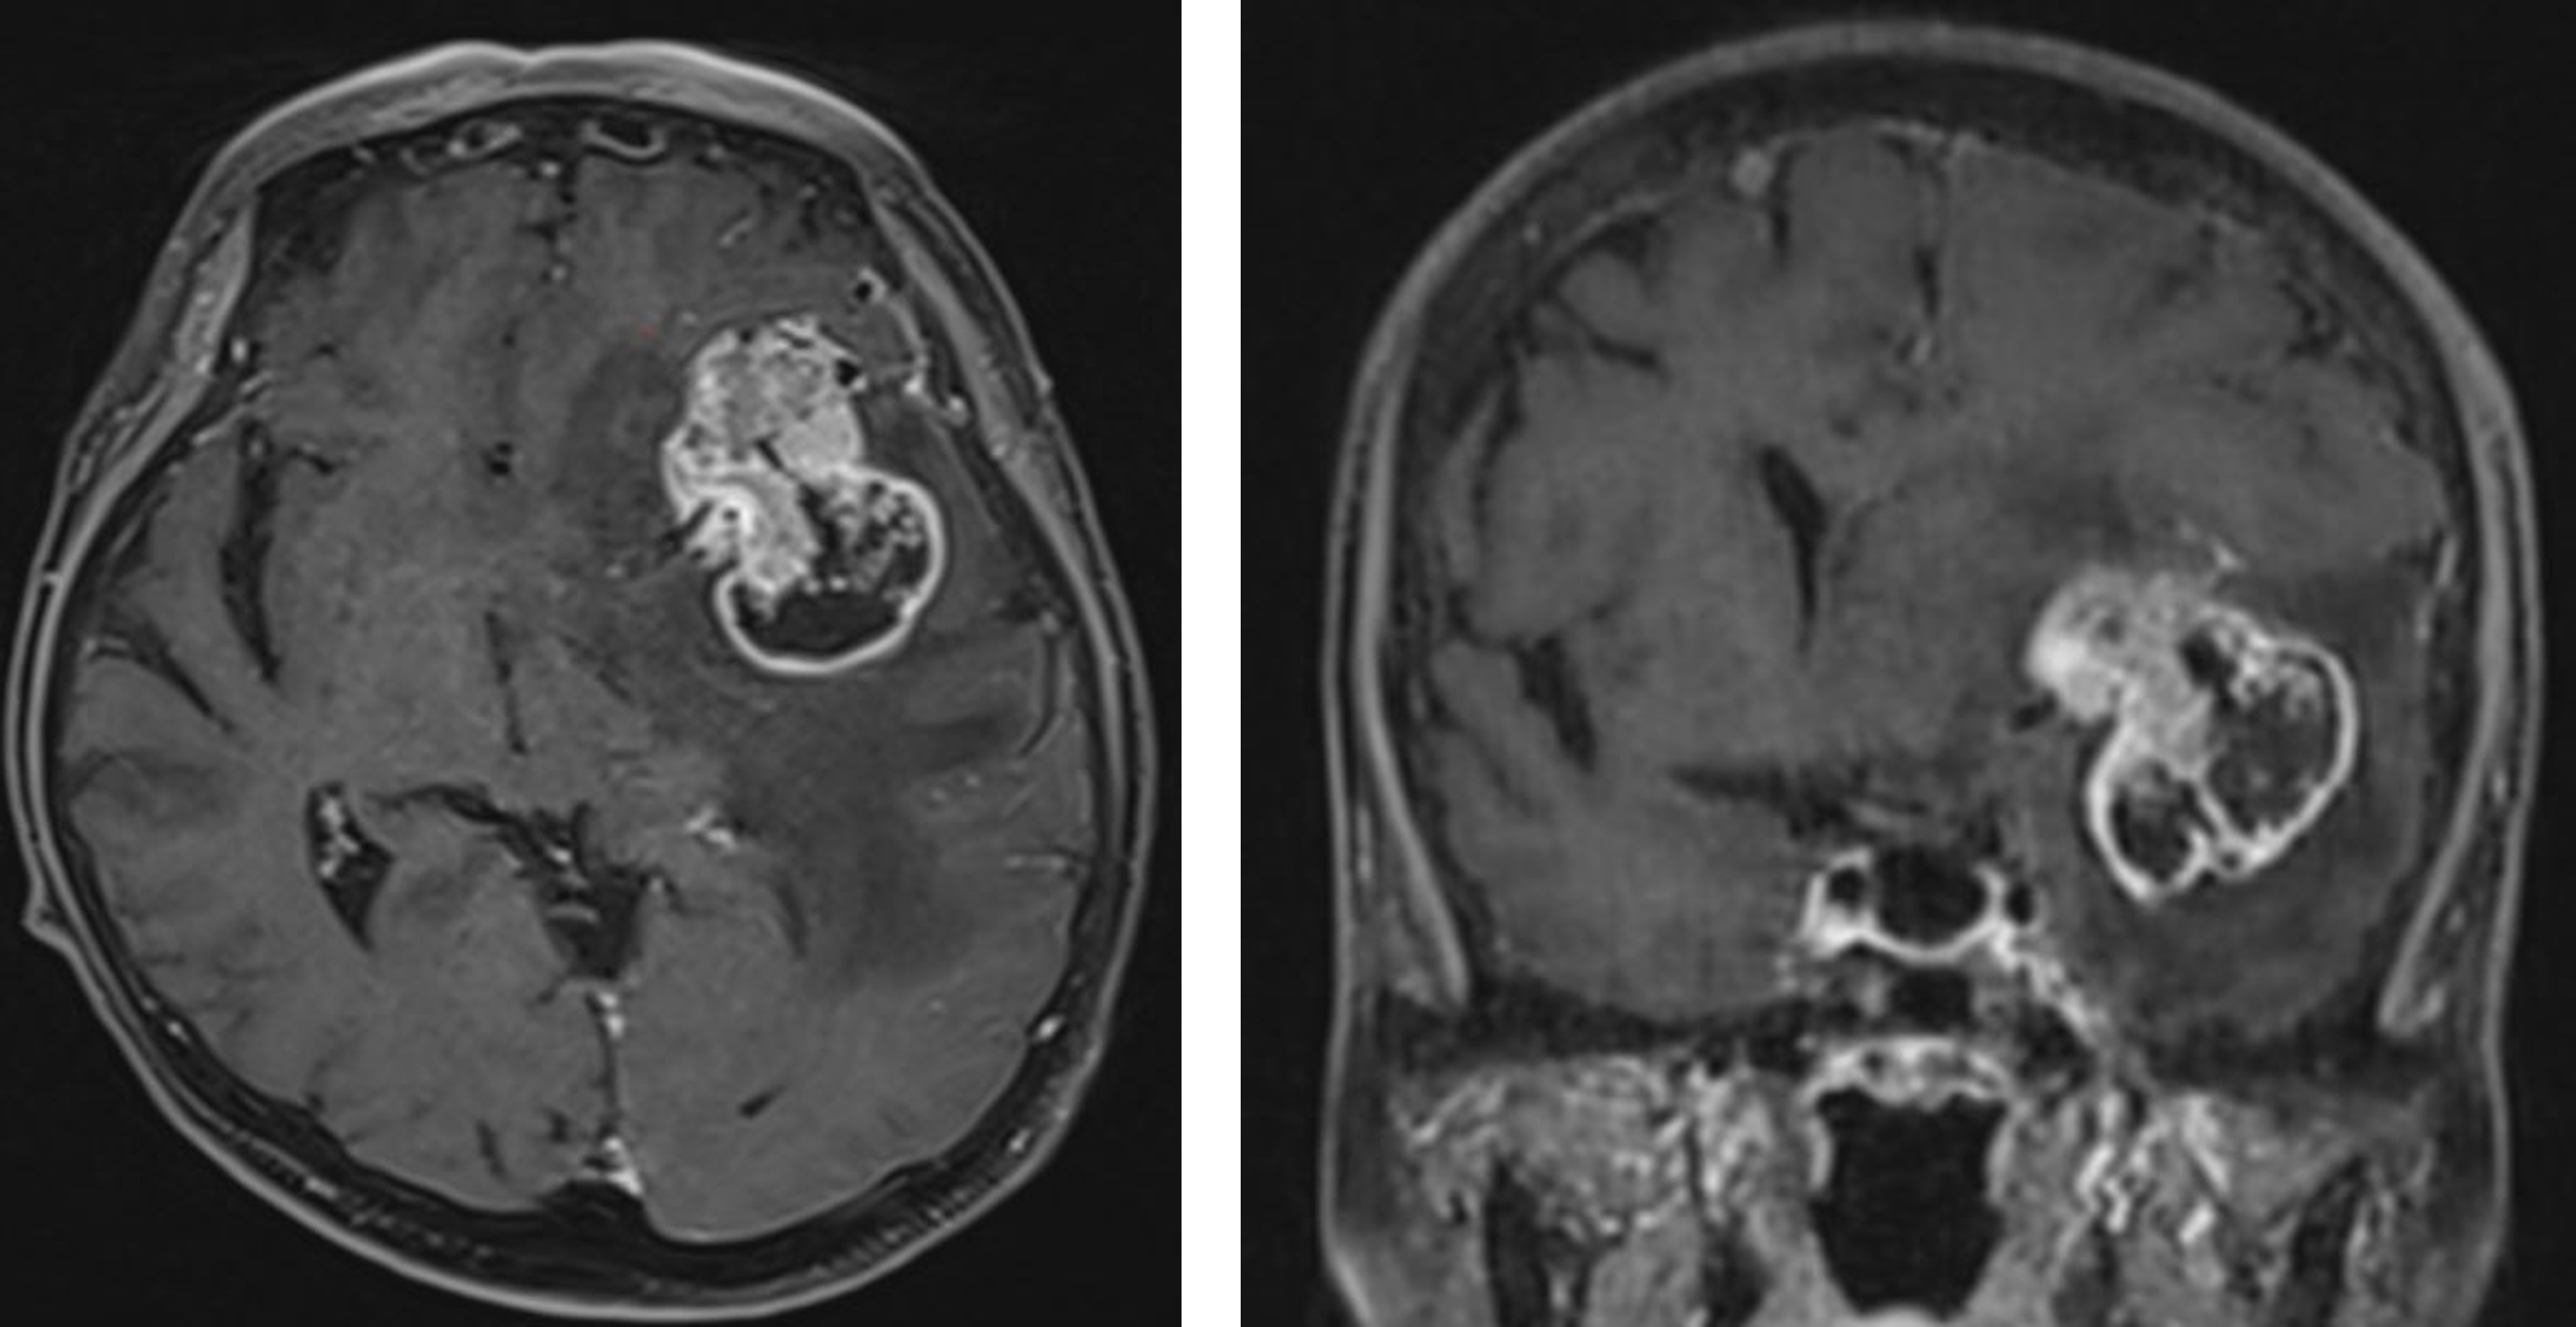

悪性神経膠腫、膠芽腫(グリオブラストーマ)

神経膠腫の中でも、膠芽腫は最も悪性度が高い腫瘍です。膠芽腫には、初発時から膠芽腫の所見を呈するもの(一次性膠芽腫)と、星細胞腫などから悪性転化して生じたもの(二次性膠芽腫)の2種類があります。大脳半球に発生することが多く、浸潤性が強い腫瘍で脳の神経線維の走行に沿って進展していきます。症状は頭痛のほか、けいれん発作、言語障害や運動麻痺などの他、性格変化、認知症などが生じることもあります。早いものは週単位で症状がどんどん悪化していきます。治療のはじめは手術で、安全な範囲内で可及的に最大限の摘出を行うことが薦められます。手術後の後療法として、放射線・テモゾロミドを用いた化学療法を行っています。その他、維持療法中の電場療法についても外来で行っております。